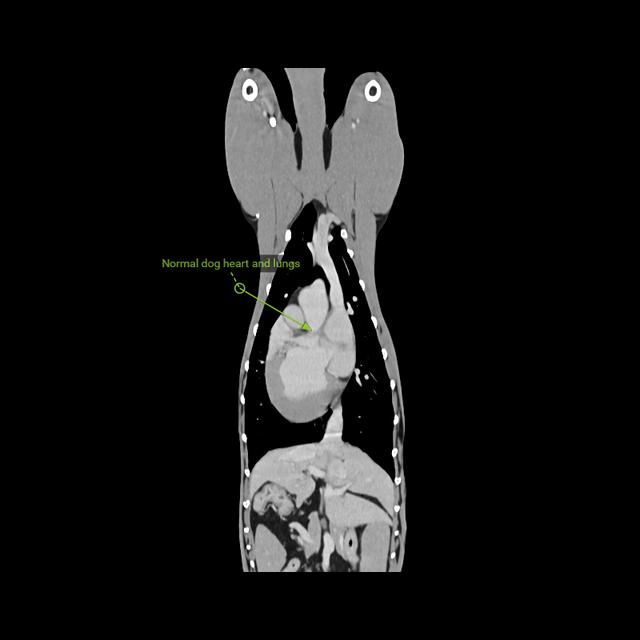

• Healthy dog heart and lungs

Here’s an image of healthy heart and lungs for comparison.

The image below shows the size of Spike’s tumour. I’ve also shared an image of healthy lungs and heart (the lungs are the black areas in the chest cavity) for comparison.